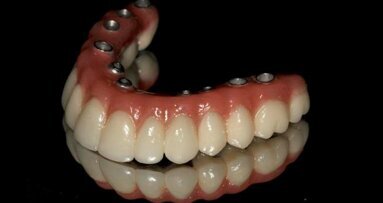

Po 7-miesięcznym okresie gojenia implanty odsłonięto i przystąpiono do wykonania ostatecznej pracy protetycznej – mostu cyrkonowego na łączniku cyrkonowym i tytanowym (Ryc. 28-31).

Szeroki wybór komponentów protetycznych umożliwia zastosowanie implantów firmy BEGO w wielu różnych sytuacjach klinicznych – od uzupełnienia pojedynczego zęba po całkowitą rekonstrukcję pełnego łuku zębowego.

Stosowanie Implantów BEGO Semados S gwarantuje przewidywalne i długoczasowe wyniki zarówno w przypadku samodzielnego zastosowania, jak i w połączeniu ze sterowaną regeneracją kości. Konstrukcja tych implantów spełnia też warunki natychmiastowego obciążenia, sprawiając, że stanowią one nowoczesny i uniwersalny system implantologiczny.